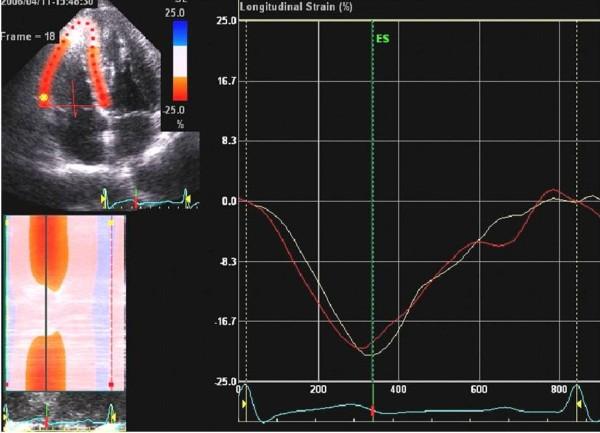

Thirty-one patients with Brugada-type ECG were studied. A pure sodium channel blocker, pilsicainide, was used to provoke an ECG response. The percentage longitudinal systolic myocardial strain at the base of both the right ventricular (RV) free wall and the interventricular septum wall was measured using 2D speckle tracking. Left ventricular (LV) and RV myocardial performance (TEI) indices were also measured.

The pilsicainide challenge provoked a positive ECG response in 13 patients (inducible group). In the inducible group, longitudinal strain was significantly reduced only at the RV (-27.3 ± 5.4% vs -22.1 ± 3.6%, P < 0.01), and both RV and LV TEI indices increased (RV: 0.19 ± 0.09 vs 0.27 ± 0.11, P < 0.05; LV: 0.30 ± 0.10 vs 0.45 ± 0.10, P < 0.01) after pilsicainide administration.

Temporal and spatial analysis using the TEI index and 2D strain imaging revealed the deterioration of global ventricular function associated with conduction disturbance and RV regional function in patients with Brugada-type ECG and coved type ST elevation due to administration of a sodium channel blocker.